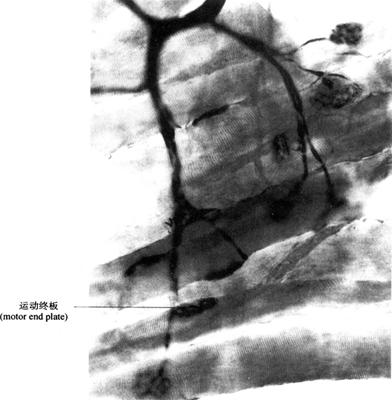

2.运动神经末梢(motor nerve ending) 是运动神经元的轴突末端终止于骨骼肌、平滑肌和腺体的终末结构。支配肌肉收缩和腺体的分泌。①躯体运动神经末梢(somatic motor nerve ending)是运动神经元的轴突,进入骨骼肌之前,失去髓鞘,反复分支,其末端呈爪状分支贴附于骨骼肌纤维的表面,称运动终板(motor end plate)(图2-59)。一条骨骼肌只接受一个轴突分支支配,一个运动神经元的轴突及其分支所支配的多根骨骼肌纤维合称一个运动单位(motor unit)。电镜下,运动终板处的肌浆丰富,有较多细胞核和线粒体,肌膜凹陷形成浅槽,轴突终末膨大陷入浅槽内,含有许多突触小泡,内含神经递质(乙酰胆碱,acetylcholine),轴突终末膜为突触前膜,富含电位门控钙通道,与其对应的肌膜为突触后膜,两者间为突触间隙。当神经冲动到达运动终板时,轴突终末突触前膜上的钙通道开放,钙离子进入轴突终末,促使突触小泡移附于突触前膜,以出胞方式释放神经递质(乙酰胆碱)与突触后膜乙酰胆碱N受体结合,引起与受体偶联的化学门控钠通道开放,大量钠离子进入肌浆内,使肌膜两侧离子分布发生变化而产生兴奋,引起肌纤维收缩。②内脏运动神经末梢(visceral motor nerve ending)是自主神经节后纤维的终末,呈串珠状膨体(varicosity),分布于平滑肌、心肌和腺体,不同的神经纤维末梢释放的神经递质不同,当神经冲动到达膨体时,膨体释放递质,通过弥散方式作用于效应细胞膜上受体,这种无典型的化学性传递称非突触性化学传递。支配内脏平滑肌、心肌的收缩及腺体的分泌。

图2-59 运动终板(400×)